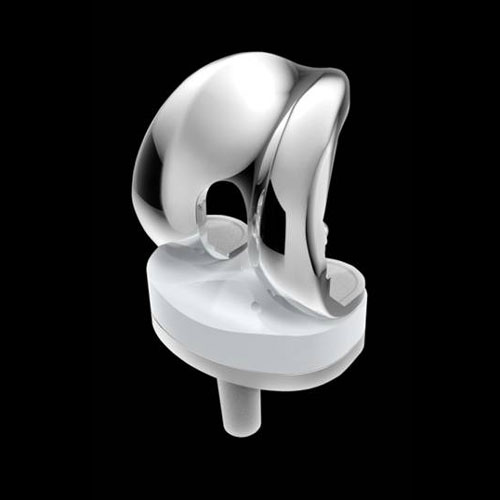

Nato a Roma nel 1953, laureato in Medicina e Chirurgia, specialista in Ortopedia, attualmente Dirige la Struttura Complessa di Ortopedia e Traumatologia presso l’Ospedale Cristo Re, Roma e presso la Casa di Cura Paideia. Si occupa di Ortopedia con particolare riferimento alla chirurgia artroscopia e protesica anche con l’uso del navigatore e di Traumatologia.